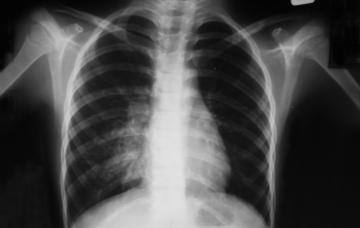

Diagnóstico del neumotórax

Para el diagnóstico de neumotórax es clave el tipo de dolor que refiere el paciente y la exploración física, junto a pruebas como radiografía de tórax y TC.